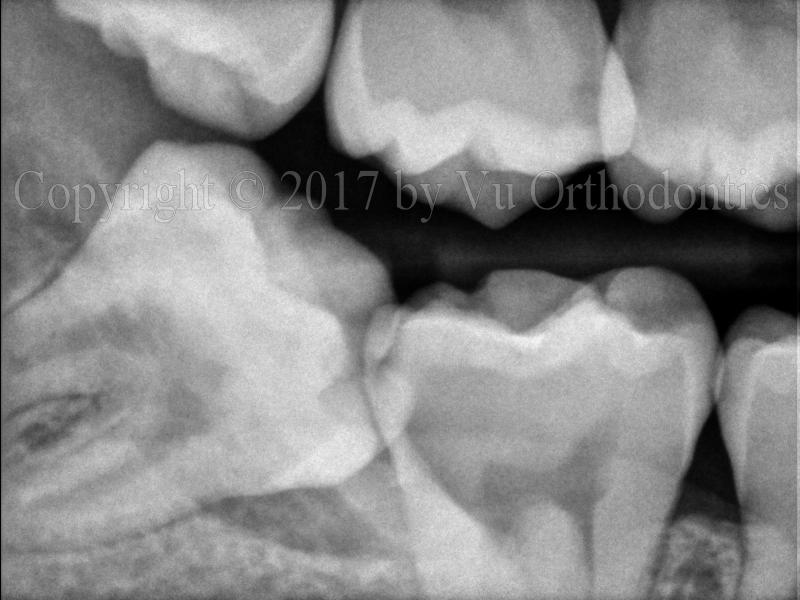

For impacted wisdom teeth, especially on the lower, doing nothing is a bad option. Figure 5 shows the damages to the lower 2nd molars by the corresponding lower wisdom teeth.

(a)

(b)

Fig. 5 Damages to the lower 2nd molars by the wisdom teeth: (a) damaged lower right 2nd molar, (b) damaged lower left 2nd molar.

Another example of damages to the lower 2nd molars by the lower wisdom teeth is shown in Fig. 6.

Fig. 6 Damages to the lower 2nd molars (Teeth #31 & #18) by the wisdom teeth (Teeth #32 & #17): (a) panoramic radiograph, (b) Tooth #31 is the lower right 2nd molar; Tooth #18 is the lower left 2nd molar